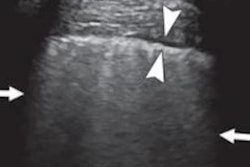

Sultan and colleague Chandra Sehgal, PhD, reviewed lung ultrasound findings of adult and pediatric patients with COVID-19 from 14 sources, including case reports and prior studies. They found common features of COVID-19 on ultrasound scans, which included multiple B-line patterns with spared areas and thickened, irregular pleural lines.

Many of the ultrasound findings were bilateral and posterobasal predominant, they noted. Scans also revealed subpleural consolidations, which can be associated with discrete, localized pleural effusion.

More specific findings related to COVID-19 included that patients with severe, progressive disease often had the presence of alveolar consolidation with a tissue-like appearance, as well as dynamic and static air bronchograms on ultrasound scans.